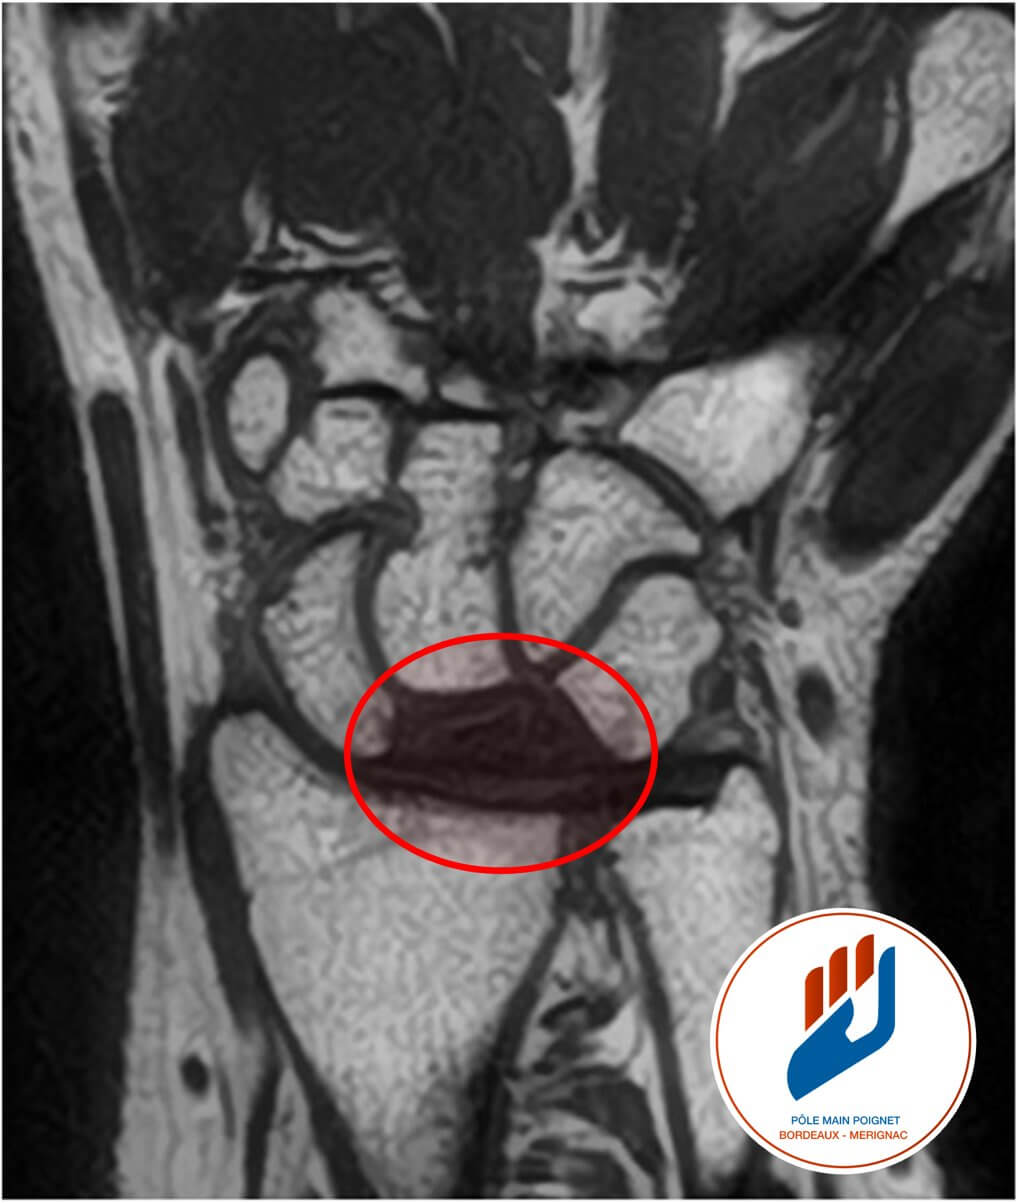

L’IRM est beaucoup plus sensible pour détecter les signes précoces de la nécrose avasculaire. Elle permet d’observer les changements dans la structure osseuse (œdème osseux) et de détecter la présence de liquide dans l’articulation.

La scintigraphie osseuse, quant à elle, peut également être utilisée pour identifier des zones de mauvaise circulation sanguine dans l’os lunatum. Ces techniques d’imagerie sont complémentaires et permettent au médecin de poser un diagnostic précis et de suivre l’évolution de la maladie au fil du temps.

Dans les formes avancées de la maladie de Kienböck, lorsque le lunatum est gravement endommagé mais encore potentiellement sauvé, il est possible de recourir à une greffe osseuse vascularisée. Cette technique de pointe, réalisée sous microchirurgie, consiste à prélever un fragment osseux vascularisé au niveau du radius (souvent à partir de l’artère du 4ᵉ–5ᵉ compartiment des extenseurs) et à le transférer dans le lunatum malade.

L’objectif est de redonner un apport sanguin au lunatum, permettant :

- de favoriser sa revitalisation,

- de prévenir l’effondrement osseux,

- de ralentir l’évolution vers l’arthrose du poignet.

Cette greffe est fréquemment associée à une ostéotomie de décompression (souvent un raccourcissement ulnaire ou un allongement radial), afin de réduire les contraintes mécaniques sur le lunatum et d’optimiser les conditions de cicatrisation.

Il s’agit d’une chirurgie techniquement exigeante, réservée aux centres spécialisés tels que le Pôle Main Poignet Bordeaux Mérignac, et proposée principalement dans les stades intermédiaires (II–IIIA de Lichtman), quand le lunatum est encore partiellement viable.

Les résultats rapportés montrent une amélioration notable de la douleur et de la fonction, surtout chez les patients jeunes et actifs, avec un potentiel de préserver le poignet avant d’éventuelles solutions plus radicales (résection carpéenne, arthrodèse).